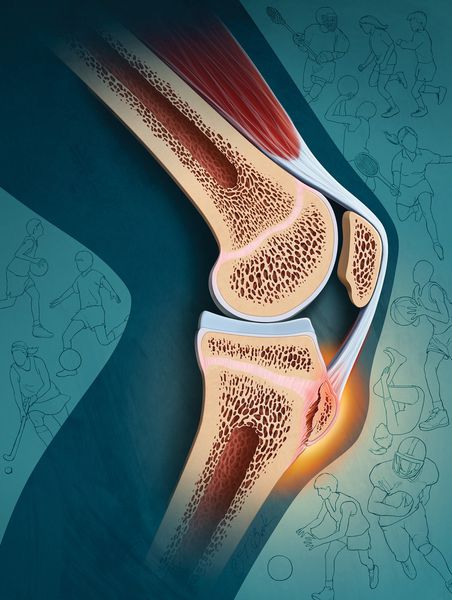

Болезнь Кёнига (рассекающий остеохондрит коленного сустава) — это очаговое идиопатическое изменение субхондральной кости, при котором примыкающей к ней суставной хрящ становится нестабильным или разрушается, приводя к изменениям самой кости. Это ортопедическое заболевание может спровоцировать преждевременное развитие остеоартрита [1] .

Рассекающий остеохондрит развивается в одном или нескольких местах формирования кости (центрах оссификации). Ему свойственна постепенная дегенерация или асептический некроз — отмирание участков костной ткани. В этот патологический процесс вовлекается как кость, так и суставной хрящ, однако в первую очередь поражается субхондральная кость [11] .

Точная причина развития этой патологии доподлинно неизвестна до сих пор. Сегодня существуют различные теории возникновения болезни Кёнгиа, включая острые травмы, повторяющиеся микротравмы, генетический фактор, ишемию и нарушение остеохондральной оссификации [5] . Чаще всего развитие заболевания провоцируют неоднократное травмирование [17] . Поэтому к факторам риска заболевания относятся занятия такими видами спорта, которые чаще всего приводят к повреждениям колена — футбол, баскетбол, гимнастика, дзюдо, вольная борьба, тхэквондо, самбо и другие [16] .